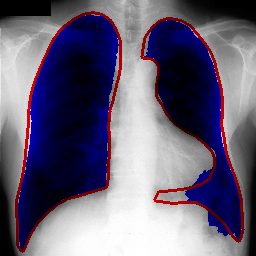

Repository features UNet inspired architecture used for segmenting lungs on chest X-Ray images.

Scores achieved on Montgomery and JSRT(With these masks. See preprocess_JSRT.py.) (Measured using 5-fold cross-validation):

| IoU | 0.971 | 0.956 |

| Dice | 0.985 | 0.972 |